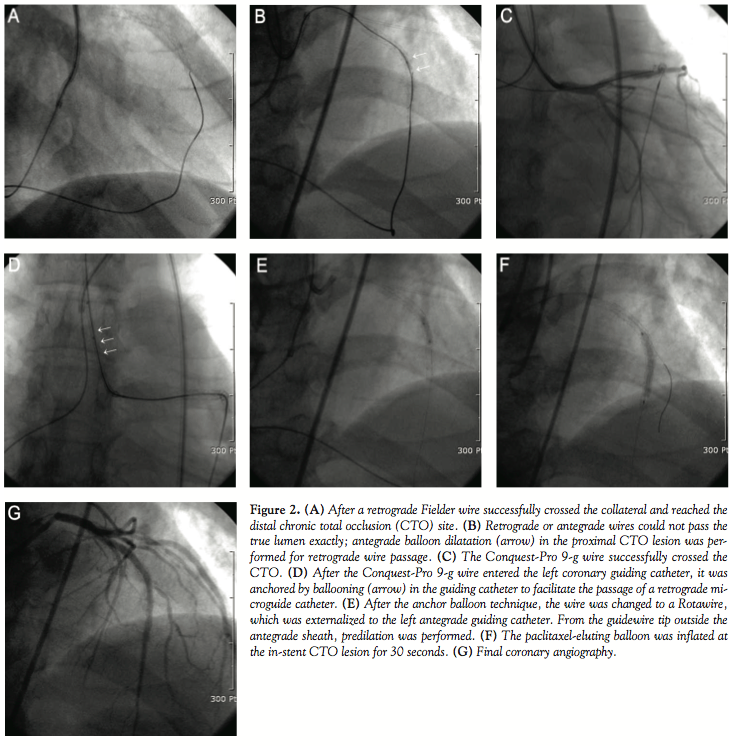

Case Report. A 56-year-old man presented at the outpatient cardiology clinic with atypical chest discomfort for several months. His coronary risk factors were hypertension and smoking. He had undergone PCI with 2 sirolimus-eluting Cypher stents (3.5 x 23 mm, 2.75 x 33 mm, consecutively; Cordis Corporation, Miami Lakes, Florida) from the proximal to the mid left anterior descending artery (LAD) in our hospital 6 years before. After intervention, he visited our laboratory regularly without chest pain and had a patent previous stent on a follow-up angiogram. The treadmill test showed ST-segment depression on stage IV. He underwent cardiac computed tomography angiography (CCTA) (Figure 1A) and repeat coronary angiography. A left coronary angiogram showed a Thrombolysis In Myocardial Infarction (TIMI) flow grade 0 with total reocclusion of the previous stent from the mid LAD (Figure 1B). The distal portion of the LAD was filled with a well-developed septal collateral connection from the posterior descending artery (PDA) on a right coronary angiogram (Figure 1C). Because the CTO had a large diagonal branch, well-visible collateral connection and a relatively long lesion, and because the approach to the septal connection was necessary to prevent harmful procedure complications such as tamponade, we planned the retrograde approach using this septal channel for PCI. The right coronary artery was first catheterized with a 7 Fr AL2 SH guiding catheter (Cordis Corporation) through the left femoral artery for retrograde access, and the left coronary artery with a 6 Fr XB 3.5 guiding catheter (Cordis Corporation) through the right radial artery. A 0.014˝, 2.8 Fr, 150 cm coronary microguide Corsair catheter (Asahi Intec, Nagoya, Japan) with a 0.014˝ Fielder FC wire (Asahi Intec) was used to negotitate the septal channel. After crossing over the septal collateral (Figure 2A), the Fielder FC wire for the retrograde approach was then changed sequentially to Miracle 3-g, Miracle 6-g and then Conquest-Pro 9-g wires (Asahi Intec) in order to cross the occluded site of the LAD. However, the hard wires could not be advanced further into the mid-LAD retrogradely. Miracle 6-g and 12-g wires were sequentially used for antegrade advancement. Since the wires could not pass the antegrade true lumen correctly, we decided to perform balloon dilatation in order to create a proximal intimal space of in-stent CTO by using 1.5 x 10 mm and 2.0 x 10 mm Sprinters (Medtronic Inc., Minneapolis, Minnesota) sequentially, with the reverse CART technique (Figure 2B). Thereafter, a retrograde Conquest-Pro 9-g wire (Asahi Intec) reached the proximal true lumen and could be advanced into the antegrade guiding catheter lumen. The retrograde wire was trapped there by a 2.5 x 15 mm Ryujin balloon (Terumo, Bangkok, Thailand), so that the microguide catheter could follow the left guiding catheter (Figures 2C and 2D). After the anchor balloon technique, the wire was changed to a 300 cm Rotawire (Boston Scientific Corporation, Natick, Massachusetts) that was inserted from the right retrograde guiding catheter to the left antegrade guiding catheter, forming a wire loop (retrograde wire externalization). From the guidewire tip outside the radial antegrade

sheath, predilation was performed with 2.5 x 10 mm and 3.0 x 15 mm Ryujin balloons (Figure 2E). Then, a 3.0 x 30 mm paclitaxel-eluting SeQuent-Please ballooning (B. Braun, Melsungen, Germany) was performed at the in-stent CTO lesion (Figure 2F), and a 2.5 x 25 mm bare-metal Coroflex-blue stent (B. Braun) was placed at a de novo distal LAD lesion. The final angiogram showed successful revascularization without periprocedural complications (Figure 2G). A 6-month follow-up angiogram showed no restenosis, and the patient remained in a stable state during the 9 months of clinical follow-up.